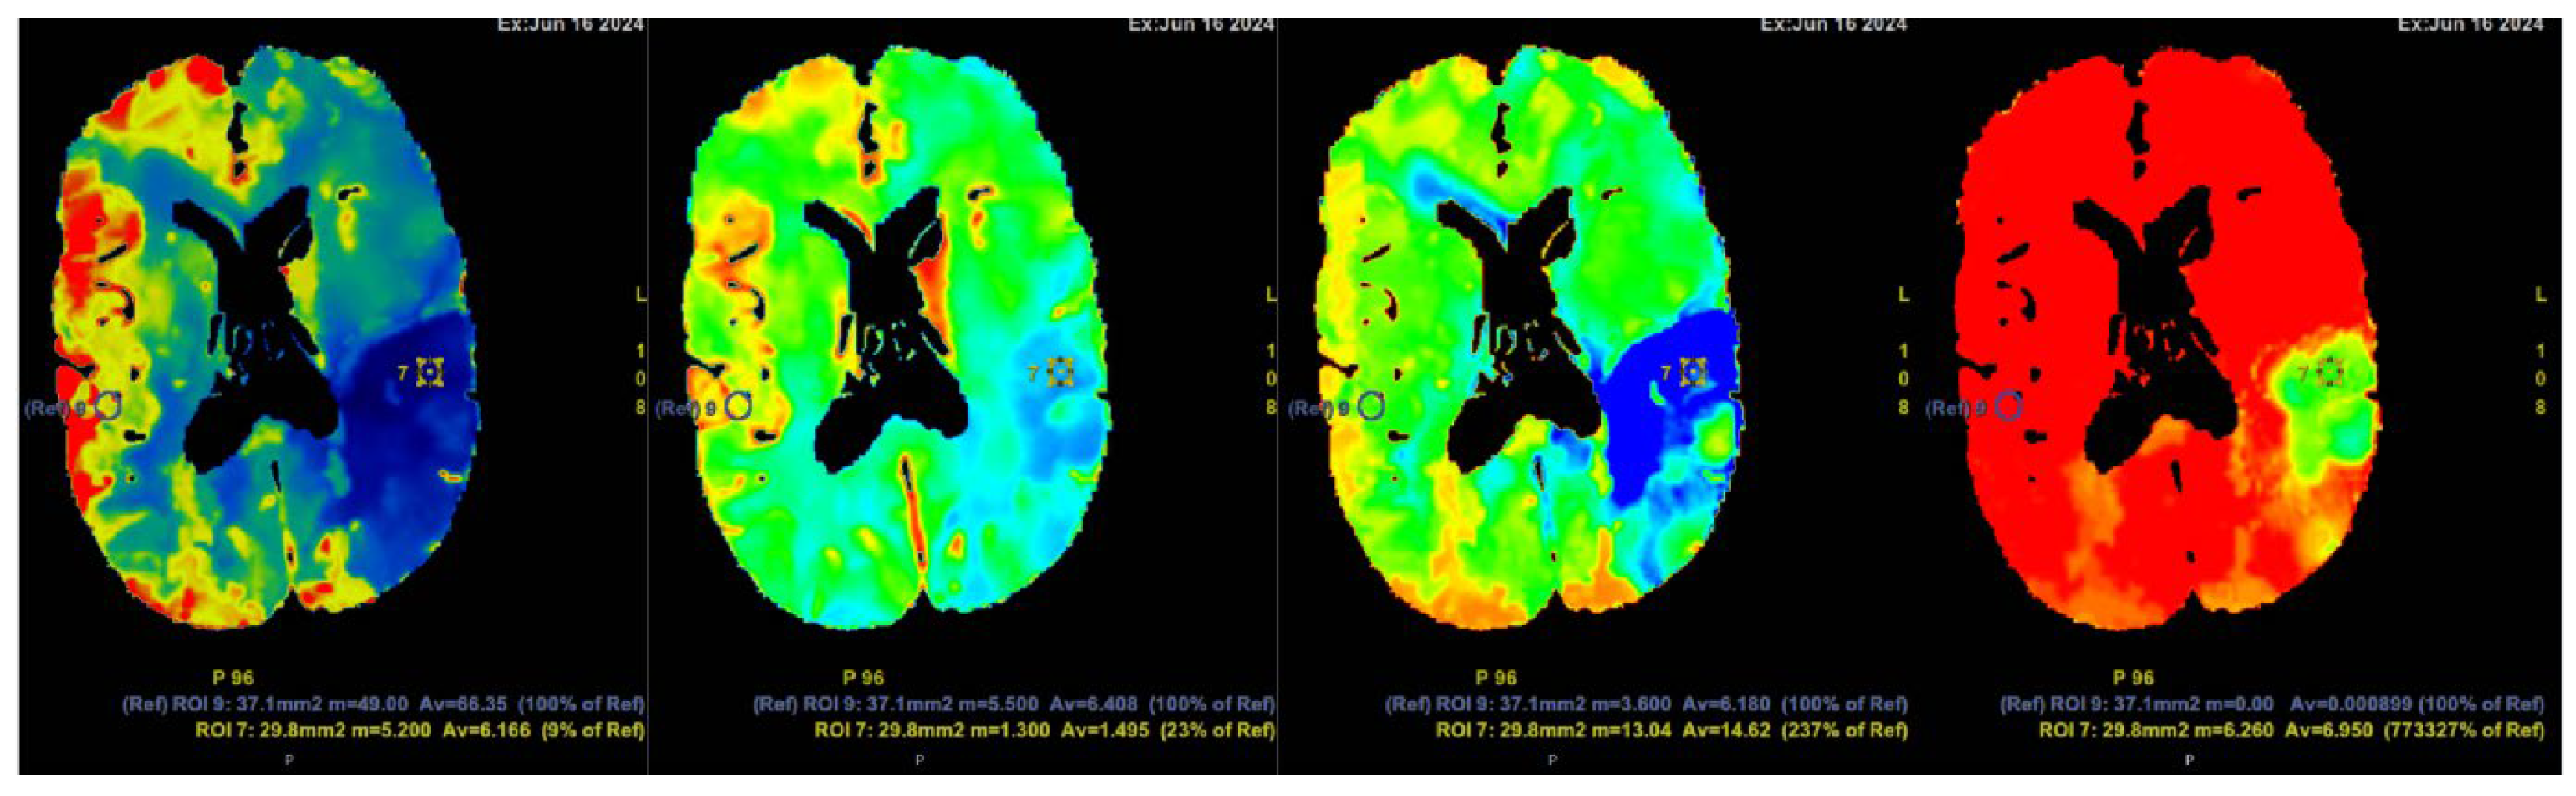

Figure 5. Computed tomography perfusion (CTP) after contrast injection shows a large hypoperfusion area in the territory of the left middle cerebral artery (ACM sin) with extensive penumbra-type damage (salvageable brain tissue) and a small core-type lesion in the parietal lobe, comprising less than one-third of the total hypoperfusion volume. The findings suggest the patient could potentially benefit from intravenous thrombolysis. Cerebral blood flow (CBF) 9%; cerebral blood volume (CBV) 23%; mean transit time (MTT) 237%.

The initial NECT radiological findings did not provide a definitive diagnosis and did not show any signs of acute ischemia. Considering the patient’s clinical presentation and initial NECT findings, further investigation with CT angiography was conducted. An acute occlusion of the M2 segment of the left middle cerebral artery (MCA) was identified, accompanied by leptomeningeal collaterals extending to the left brain hemisphere with a Tan collateral score of 3 (Figures 1, 2, 3 and 4). A subsequent perfusion CT was performed revealing an extensive hypoperfusion zone predominantly consistent with a penumbra-type lesion (Figure 5). No hemorrhage was observed. The emergency department radiologist and neurologist raised concerns regarding the possibility of an acute ischemia combined with primary neoplastic tumour and calcification of the basal ganglia, potentially a high- grade oligodendroglioma. Therefore, an acute thrombolytic therapy with intravenous thrombolysis was contraindicated. Thrombolysis is typically constrained to a standardized 4.5-hour window to optimize reperfusion outcomes and minimize the risk of ischemia-reperfusion injury [24,25]. The patient was subsequently admitted to the Stroke Unit for further evaluation and management.

In 2010, Dehkharghani et al. published an article demonstrating six case reports with unilateral caudate and putamen calcifications in DVA drainage territories. In all these patients, DVA was found in gadolinium-enhanced MRI and/or computed tomography angiography (CTA) or conventional angiography. They stressed out the venous hypertension as the main contributing factor for these abnormalities [22]. Moreover, they reported no symptoms referable to the basal ganglia, and patients they presented did not reveal underlying metabolic disorders or processes associated with calcium deposition [22]. In our case, the patient was a fifty-four-year-old male presenting with a sudden speech impairment and right-sided weakness. No abnormal movements were noted in this patient. Subacute stroke on the left side in the dorsal part of the insula, in the upper dorsal part of the left temporal lobe and partially in the left parietal lobe was found on NECT, and CTA revealed left middle cerebral artery (MCA) M2 occlusion. On CT perfusion (CTP), markedly decreased cerebral blood flow (CBF) and cerebral blood volume (CBV) was noted along with increased mean transit time (MTT). Subsequently, gadolinium-enhanced brain MRI was performed where small blood vessels draining to subependymal periventricular veins on T1 post-contrast was found. Due to these findings, the patient underwent following digital subtraction angiography (DSA) where venous angioma in the area of ​​the left basal ganglia was observed.